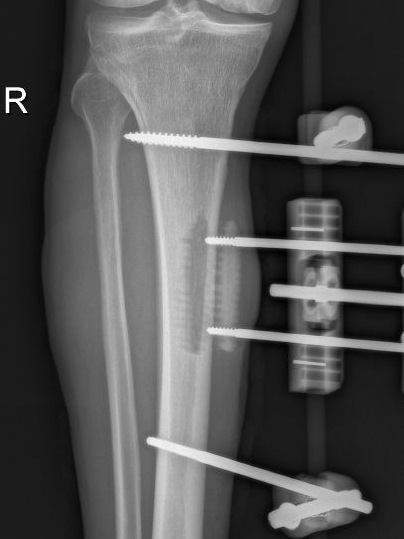

12月17日,贵州航天医院第88次晨读会由我院骨一科主任、副主任医师陈明勇作学术交流,他以“肱骨近端骨折并肩关节脱位的手术治疗”为题,全面讲解了该损伤的手术策略、术中血供保护理念及内侧支撑重建技术等内容,并通过多个典型病例图文资料分享了从损伤机制分析、手术步骤实施到术后随访评估的完整过程与关键细节,为临床处理此类复杂骨折提供了较为全面的技术参考,有助于在手术规划中结合个体情况开展针对性治疗。 贵州航天医院 骨科专家简介 陈明勇 骨一科主任,副主任医师 临床擅长:从事创伤骨科工作约20年,对骨缺损、骨不连、骨肿瘤、肢体畸形等的肢体矫形重建及功能重建,慢性化脓性骨髓炎的根治治疗、糖尿病足的保肢治疗、快速康复理念(ERAS)下的老年骨折的诊治,四肢复杂骨折的诊治,四肢骨折等微创手术治疗具有丰富的临床经验。 2004年毕业于遵义医学院临床专业,曾在中国人民解放军总医院、广西医科大学第一附属医院、上海第六人民医院骨科进修。中国中西医结合学会骨伤科专业委员会横向骨搬移治疗糖尿病足及微血管网再生学组首届委员,遵义市医学会创伤分会常务委员。 瞿 晖 骨科党支部书记,骨二科主任,副主任医师 临床擅长:对骨科的常见病、关节外科、脊柱外科及运动医学疾病的诊治具有丰富的临床经验,熟练掌握骨科手术操作技术。 毕业于遵义医学院临床医学系,2005年前往广州中山大学第一附院骨显微医学部进修学习,2011年前往成都华西医院进修学习,并多次在省内外学习骨科相关知识,是中华医学会骨科分会会员。 赵小锋 中共党员,骨二科副主任,副主任医师 临床擅长:从事骨科临床工作11年,对骨科常见病、多发病诊疗有较为丰富的临床经验,擅长脊柱相关疾病诊断及治疗,尤其是颈、腰、腿疼痛疾病诊断及治疗,擅长胸腰椎骨折微创经皮穿刺内固定术、经皮穿刺椎体成形术、经皮穿刺脊柱内镜下腰椎间盘摘除术、单纯开创腰椎间盘摘除术、腰椎滑脱复位椎间植骨椎融合内固定术、腰椎管狭窄减压融合内固定术及人工髋、膝关节置换术等。 2012年毕业于遵义医学院外科学专业硕士研究生,2019年参加“遵义市115医学人才精英计划”于上海交通大学第一附属医院培训学习,2023年于北京大学第三人民医院脊柱外科进修学习,曾获得遵义市优秀医师荣誉称号。 遵义市手外科第一届委员,遵义市医学会创伤分会第一届委员,遵义市医学会创伤分会第二届委员,贵州省康复医学会第三届脊柱脊髓专业会委员,遵义市医学会烧伤与整形外科学分会委员,发表论文5篇,其中国家级核心期刊1篇,SCI论文1篇,主持市级课题1项并结题,参与市级课题2项。 赵兴东 骨科主任医师 临床擅长:擅长骨科的常见病及各种创伤、四肢骨折创伤修复、骨感染、手足疾病的诊治和手足体表畸形的矫形整复,熟练掌握骨科四肢骨病及创伤的手术操作技术,尤其在四肢关节复杂性损伤、手足外伤、组织缺损创面、难治创面的皮瓣修复方面及平足、高弓足矫形方面及四肢慢性疼痛诊治、康复方面具有丰富的临床经验。 硕士研究生,毕业于遵义医学院临床外科系,2015年前往山东省立医院手足外科进修学习;遵义市医学分会创伤分会第一、二届委员,遵义市手外科医学会第二委届员会常务委员;在省级及省级以上期刊发表文章9篇,参编著作2部,参与主持并完成市级课题1项,参与市级课题2项、省级课题1项。 张艳金 中共党员,骨科副主任医师 临床擅长:从事骨外科工作16年,对复合伤、多发伤的救治、四肢骨干骨折、关节周围骨折、骨肿瘤、骨髓炎等诊治具有丰富的临床经验。 中共党员,硕士研究生,2006年本科毕业于山西医科大学第二临床医学院,2011年研究生毕业于北京军区总医院;在“老年COPD患者合并髋部骨折的诊治”国际合作课题组研究两年,在老年髋部骨折的诊治方面具有丰富的经验,并发表论文6篇;主持遵义市级课题1项,承担遵义医科大学的临床教学工作,获得遵义医科大学优秀带教老师荣誉。编撰有《骨科疾病诊疗精粹》一书,开展2项新技术,编撰地方规范《务川自治县创伤骨科常见疾病诊疗规范》一书。 张俊凯 骨科副主任医师 临床擅长:从事骨科临床工作28年,对创伤骨折、骨感染、骨缺损、骨不连等外科诊治,四肢骨折的微创手术治疗,四肢复杂骨折(如关节内粉碎性骨折、多发骨折等)的损伤控制及手术治疗等具有丰富的临床经验。 1995年毕业于遵义医学院临床专业,2009年前往复旦大学附属医院骨科进修1年。 卢懿明 中共党员,骨科副主任医师 临床擅长:从事骨科工作18年,对创伤骨折、四肢骨折的微创手术治疗、四肢复杂骨折(如关节内粉碎性骨折、多发骨折等)的损伤控制及手术治疗,尤其是髋部骨折的PFNA等微创技术,踝关节骨折、膝关节周围骨折的Mipo微创技术等具有丰富的临床经验,开展了4项新技术,发明6项新型专利技术。 2005年毕业于遵义医学院临床专业,2017年,前往南方医科大学第三附属医院骨科进修半年,回院后运用Mipo技术对骨干骨折及干骺端骨折的治疗技术,同时积极开展骨盆骨折、髋臼骨折腹直肌外侧切口的应用;发表了多篇专业论文,经常参与省内外学术交流会授课,获得医院荣誉称号多个。 邬夏荣 骨科副主任医师 临床擅长:从事骨科工作16年,对四肢复杂骨折、骨肿瘤的诊治,尤其是足踝创伤、慢性踝关节损伤、平足症等诊疗具有丰富的临床经验。 2006年毕业于遵义医科大学临床医学专业,曾在陆军军医大学西南医院进修学习,发表多篇骨科学术论文。 余德怀 中共党员,骨科副主任医师 临床擅长:从事骨科工作10余年,对运动医学、骨关节、脊柱外科常见病、多发病的诊治具有丰富的临床经验。 硕士研究生,2011年毕业于遵义医学院临床医学专业,曾前往遵义医科大学附属医院运动医学专业进修学习;是贵州省医学会运动医学分会青年委员,西部关节镜联盟委员;发表多篇骨科学术论文。 冯 乾 骨科副主任医师 临床擅长:从事骨科工作近20年,熟练掌握骨科多发病及常见病的诊治,尤其对脊柱退变性疾病的诊断及治疗具有丰富的临床经验,主要研究脊柱微创相关治疗方式,能熟练开展椎间孔镜及UBE。 曾前往北京大学第三医院进修学习疼痛及椎间孔镜、首都医科大学友谊医院专业进修脊柱内镜;是贵州省康复医学会第三届脊柱脊髓专业委员会委员;发明专利3项、发表脊柱外科专业论文多篇。 贵州航天医院骨科简介 基本情况 贵州航天医院(原3417医院)骨科组建于1968年,前身是以创伤和断肢(断指)再植闻名于世的上海市第六人民医院骨科,中国断肢(断指)再植的奠基者、中科院院士陈仲伟等专家莅临科室指导医疗和教学,并在70年代开展了贵州省首例断肢(断指)再植手术。组建50余年来,诊治患者已逾百万,挽救了无数的伤病员,成为了保障遵义地区人民群众健康的重要支撑。 经过几代人的不懈努力,今天的骨科,已由创伤骨科发展至骨病、骨肿瘤、骨结核等领域,现有脊柱外科、关节外科、四肢创伤、手足外科四个亚专科,成为了集医疗、教学、科研于一体的综合学科,是贵州省临床重点专科、遵义市临床重点专科、遵义市骨科临床医学中心、遵义市基层骨科专科联盟理事长单位。 科室目前开放床位110张,共有医护人员50余人,副高级以上专家18人,硕士研究生15人。拥有一流骨科医疗设备多台,每年不定期选派优秀技术骨干到全国各大知名医学院校进修、学习、参观、交流,并邀请国内、国外知名专家教授来院进行交流、指导,通过不断引进国内外先进的诊疗技术,科室医疗技术水平稳步提升,为广大人民群众提供了优质的医疗服务。 专科特色 骨一科 (一)骨缺损、骨不连的肢体与功能重建 胫骨横向骨搬移技术治疗糖尿病足: (二)慢性骨髓炎的根治治疗 (三)肢体缺血性疾病如糖尿病足、脉管炎的保肢治疗 (四)皮瓣修复 (五)复杂创伤的治疗 (六)老年髋部骨折及小儿骨折快速手术 老年髋部骨折: 骨二科 (一)胸腰椎骨折微创经皮椎弓根螺钉固定术 (二)老年性骨质疏松性患者腰椎滑脱脊柱内固定术(骨水泥螺钉) (三)V形双通道脊柱内镜技术(VBE)腰椎融合术治疗腰椎退行性疾病 (四)老年性骨质疏松性骨折(PVP/PKP)术 (五)人工髋关节置换术 (六)双侧股骨头坏死人工全髋关节置换 (七)右侧全髋置换术后假体周围骨折翻修 (八)人工膝关节置换术 (九)人工膝关节假体松动翻修 (十)关节镜技术 传统手术切口 关节镜技术切口 诊疗范围 骨一科 1.四肢创伤、矫形。 2.手、足踝外科。 骨二科 end